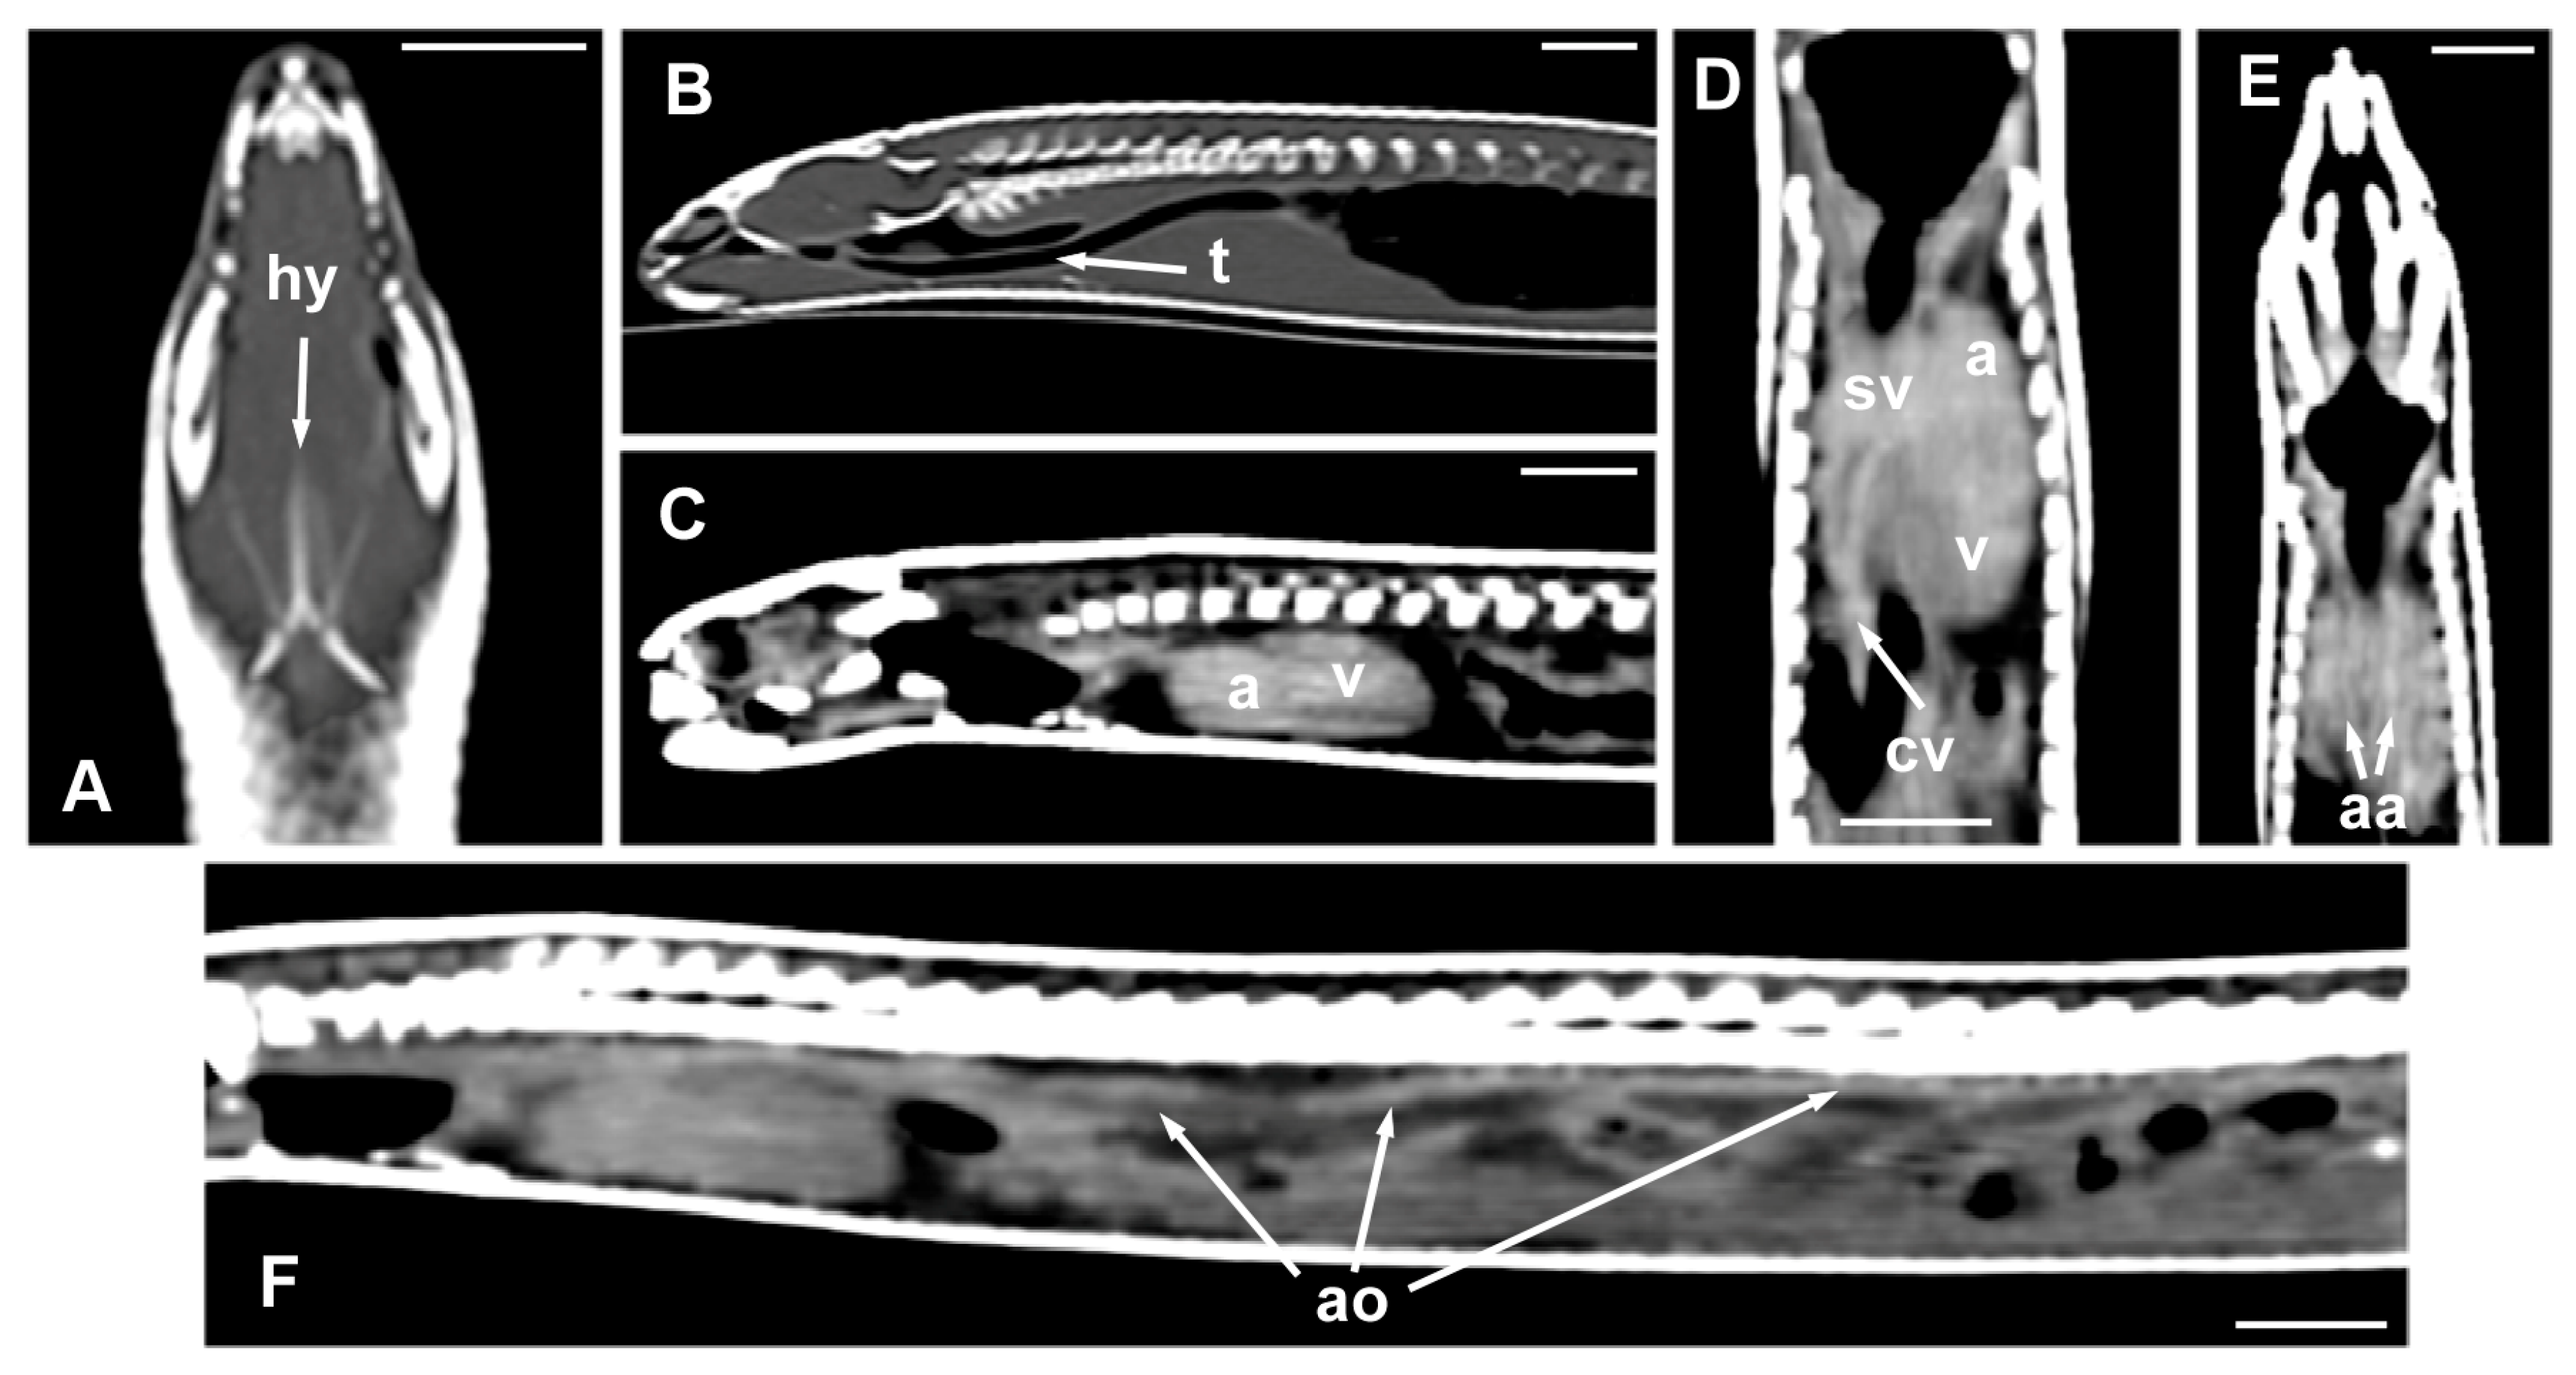

The morphology of the hyoid bone was most clearly observed in the dorsal plane, in the CT images obtained from the MPR reconstruction (Figure 6A). The trachea was clearly distinguished as a tubular structure containing gas in the lumen, extending from the glottis to the main bronchial bifurcation; the sagittal plane allowed the visualization of its entire length (Figure 6B). The heart and some great vessels were best identified in postcontrast images (Figure 6C–F). The dorsal and sagittal planes were the most suitable for observing the slight distinction between the atria and the ventricle of the heart (Figure 6C,D). On the contrary, the sinus venosus, the two cranial cava veins, and the aortic arches were most clearly observed in the dorsal plane (Figure 6D,E). The aorta was identified along the midline, just ventral to the spine, and was best observed in the sagittal plane (Figure 6F). The pulmonary trunk, divided into the left and the right pulmonary arteries, and the thyroid gland, were not identified in the CT images.

Figure 6.

The CT images of Pseudopus apodus in the dorsal (A,D,E) and sagittal (B,C,F) planes showing the hyoid bone (A), the trachea (B), the atria and ventricle (C,D), the sinus venosus and the two cranial cava veins (D), the aortic arches (E), and the dorsal aorta. The images (C–F) were obtained after contrast media administration. See the list for abbreviations. Bar = 10 mm.

In general terms, the internal organs in many serpentiform species are elongated, arranged sequentially, or even compressed laterally. This is also true in the case of the Pseudopus apodus. Once the animal is opened, along the ventral midline, the presence of two powerful masticatory muscles (pterygoideus muscles) (Figure 5A,B), together with the hyoid bone that provides support to the tongue (Figure 5A), is notable. Only a portion of the hyoid bone can be seen in a dissection, compared to the full shape of the in situ bone with CT imaging (see below). The trachea is a membranous and cartilaginous flexible duct that extends from the larynx to the entry of the thoracic cavity (Figure 5A–D). As in other lizards, the tracheal rings are incomplete. Parallel to this, it is possible to identify the presence of two cranial cava veins. The heart is elongated and conically shaped, with two atria and a single ventricle (Figure 5B). There are two aortic arches (left and right), emerging from the heart, and a pulmonary trunk, which is subsequently divided into two pulmonary arteries (right and left). The aortic arches join to form the dorsal aorta, which runs through the entire coelomic cavity (Figure 5B,C). Immediately above the heart, it is possible to see the thyroid gland, which is small and rounded (Figure 5D).

Figure 5.

The images of the dissection of Pseudopus apodus in the ventral plane showing the hyoid bone (A), the trachea (A–D), the cranial cava vein, and aortic arches (B), the atria and ventricle (A,B), and the thyroid gland (D). See the list for abbreviations. Bar = 10 mm.